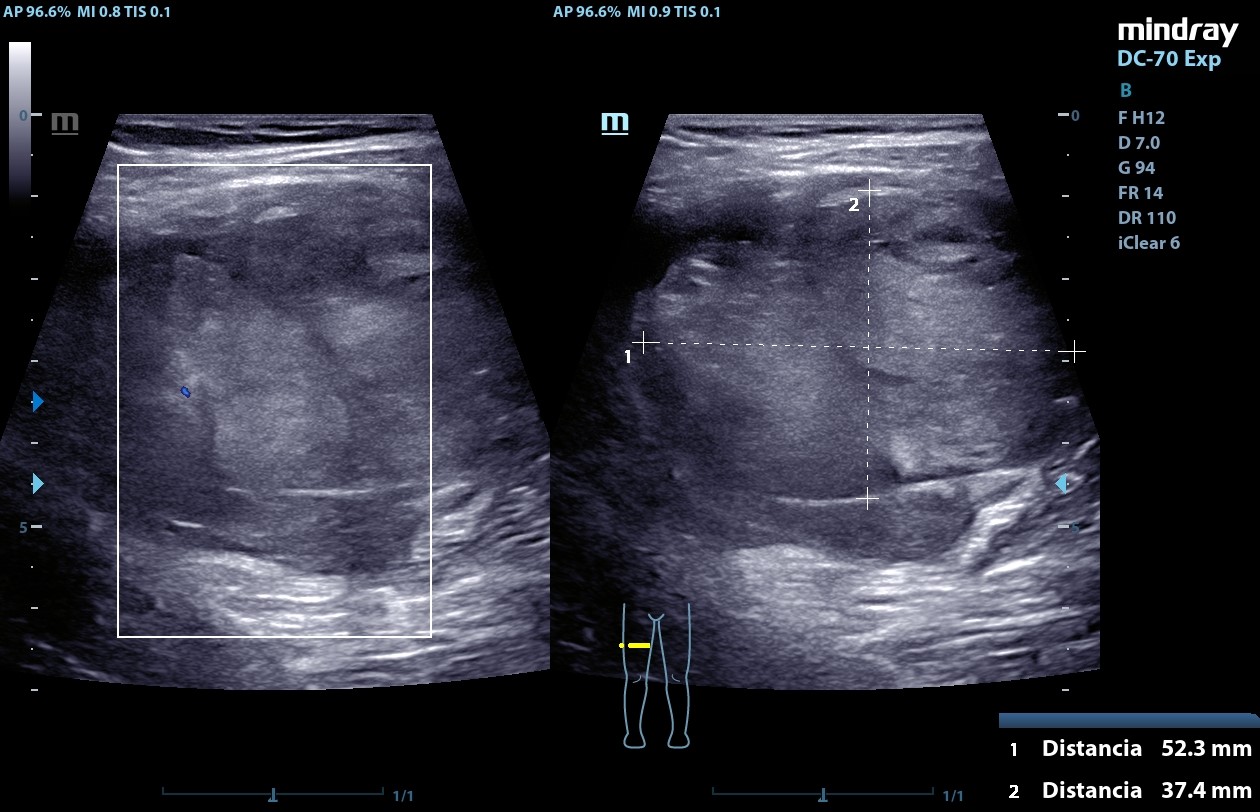

Ecografía POCUS (20/09/24): masa heterogénea de centro hiperecogénico, de bordes bien definidos, Doppler negativa de aproximadamente 52,3 mm x 37,4 mm x 67,3 mm compatible con neurofibroma plexiforme.

La ecografía es la técnica de elección para el diagnósitico de la mayoría de los tumores de partes blandas, y aunque es poco específica para el diagnóstico del neurofibroma plexiforme (habitualmente se presenta como una lesión hipoecogénica de límites bien definidos, que parecen un "tiro al blanco", como una masa fusiforme de centro hiperecogénico rodeada por tejido hipoecogénico) es importante conocerlo y saber identificarlo debido a su potencial de malignización.